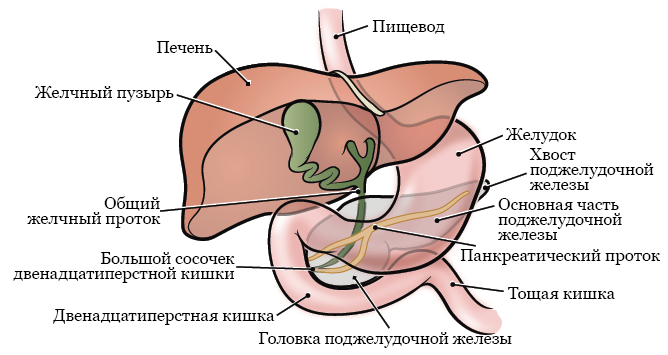

Фотографии медицинских исследований инсулиномы и синдрома Триады Уиппла